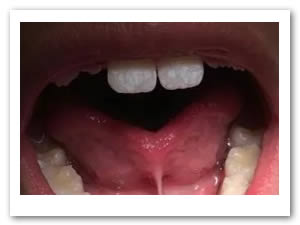

• Se realizó prueba para ratificar la proyección lingual la cual fue exitosa (Figura 10).

Figura 10. Prueba exitosa de tracción lingual